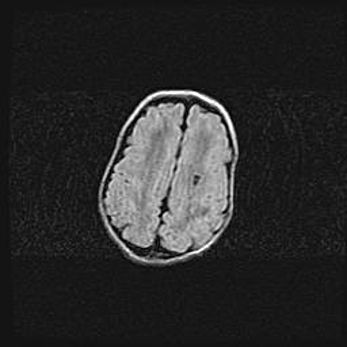

Лейкомаляция с кистозно-глиозной дегенерацией головного мозга.

Возраст: 2 месяца 25 дней

Вес: 6400 г

Окружность головы: 40 см

Срок гестации: 41 неделя

Лейкомаляцию относят к ишемически-гипоксическим повреждениям головного мозга, диагностируемым у новорожденных. При лейкомаляции в головном мозге обнаруживают очаги некроза, возникшие после тяжелой гипоксии и нарушения кровотока. В процессе морфогенеза очаги проходят три стадии: 1) развития некроза, 2) резорбции и 3) формирования глиозного рубца или кисты. Перивентрикулярная лейкомаляция (ПЛ) встречается примерно в 12% случаев среди новорожденных, обычно – у недоношенных детей, причем, частота ее зависит от массы, с которой младенец появился на свет. Наибольшее число малышей страдает лейкомаляцией, если масса при рождении 1500-2500 г.